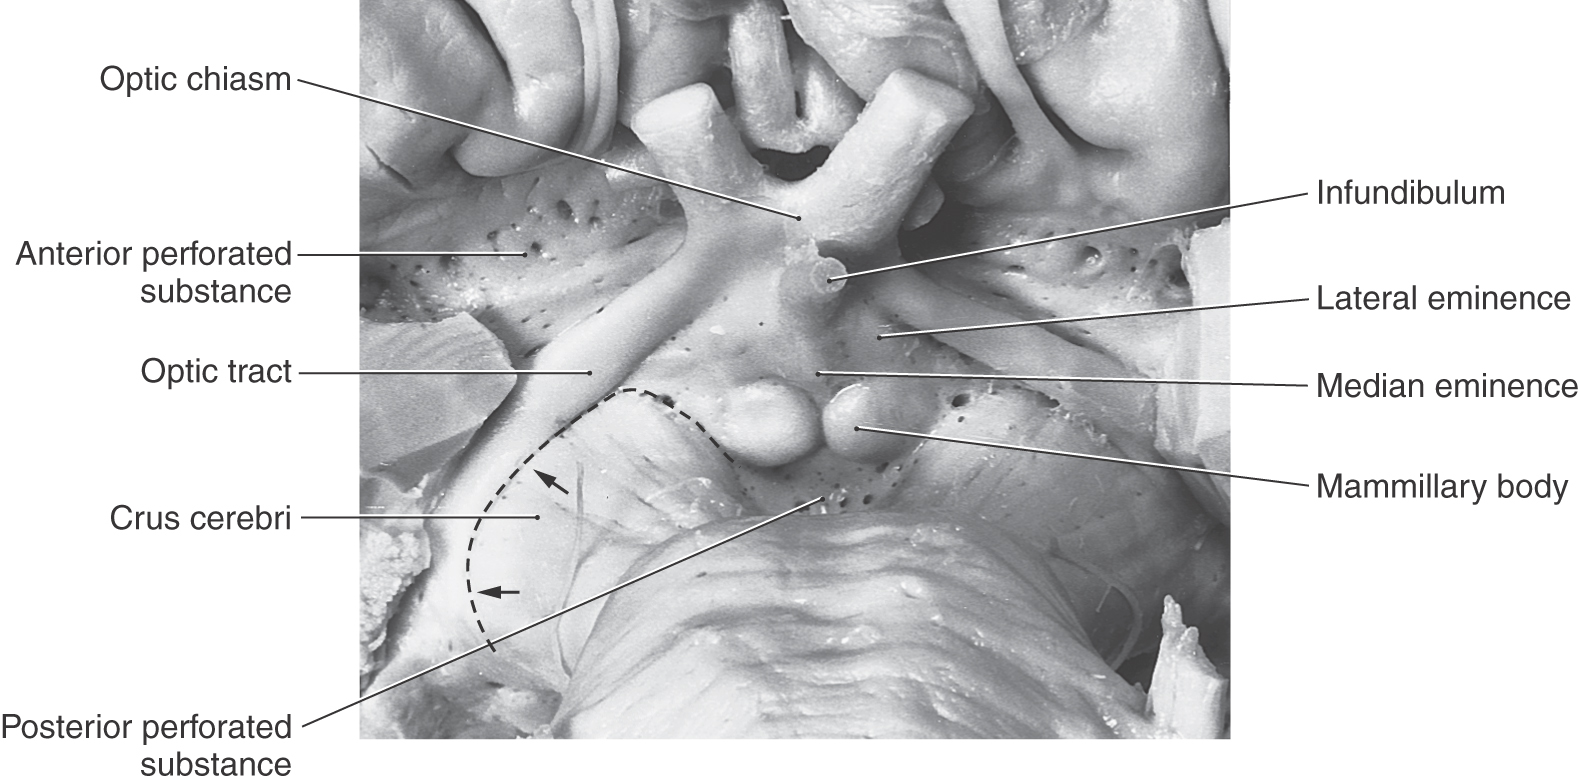

image

Figure 15-5. Anterior (ventral) view of the hemisphere emphasizing diencephalic structures visible on the surface and showing the diencephalic-mesencephalic interface as represented by the caudal edge of the optic tract (arrows).

All four diencephalic subdivisions can be approximated in a midsagittal section of the forebrain (Figs. 15-4 and 15-6). The dorsal thalamus is located superior to the hypothalamic sulcus and extends from the interventricular foramen caudally to the level of the splenium of the corpus callosum. The hypothalamus lies inferior to the hypothalamic sulcus and is bordered rostrally by the lamina terminalis and caudally by a line that extends from the posterior aspect of the mammillary body superiorly to intersect with the hypothalamic sulcus. The only diencephalic structures visible on the inferior surface of the hemisphere are those related to the hypothalamus, including the optic chiasm, infundibulum, medial and lateral eminences, and mammillary bodies (Fig. 15-5). The ventral thalamus (subthalamus) does not border on the ventricle; rather, it occupies a position caudal to the hypothalamus, rostral to the diencephalon-midbrain junction, and lateral to the midline (Figs. 15-4 and 15-7B). Epithalamic structures are located posteriorly and caudally, in close apposition to the posterior commissure, and include the pineal gland, the habenular nuclei, and the main afferent bundle of these nuclei, the stria medullaris thalami.